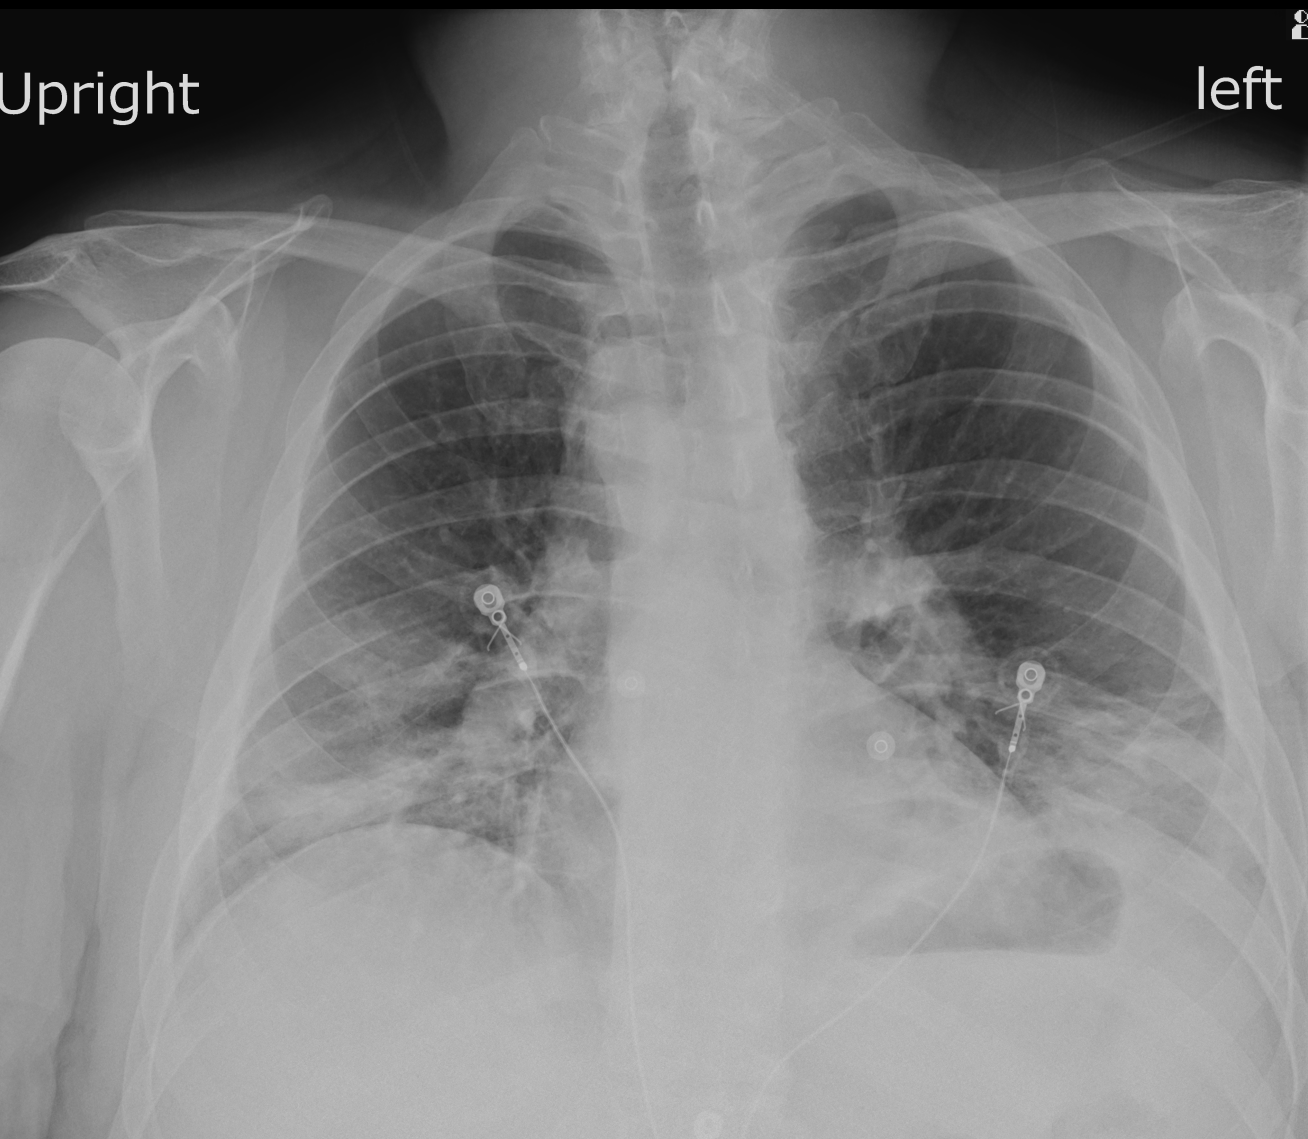

A 43-year-old male presents for suspected PE evaluation. What is the diagnosis?

Case submitted by Soham Shah, M.D., with Texas Radiology Associates.